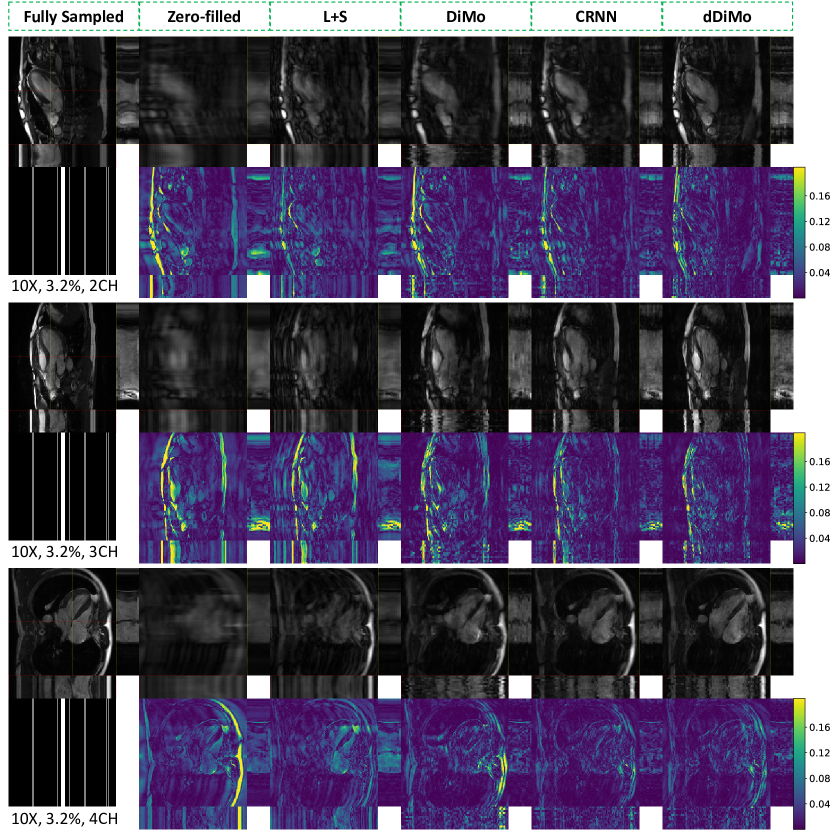

4.1 Results of Cardiac Cine

Exemplary reconstructions from various methods for cine images at different acceleration factors and cardiac views are shown in Figure 4, Figure 5, and Supporting Information Figure S1 and Figure S2. The proposed dDiMo method demonstrates superior performance in artifact suppression, detail preservation, and accurate cardiac motion capture, producing sharp and clear reconstructions. In contrast, competing methods, including L+S, DiMo, and CRNN, exhibit notable artifacts, spatial blurring, and temporal misalignment, particularly at higher acceleration factors. Exemplary - profiles extracted along the vertical yellow dashed line and horizontal red dashed line, as indicated by the yellow and red dashed rectangles on the spatial reconstruction images, are presented to illustrate temporal alignment across cardiac frames. Reconstructions from dDiMo achieve better alignment along the cardiac phase, with clearer boundary definitions that closely resemble the fully sampled reference image compared to other methods. These observations are further supported by error maps of the reconstructed spatial images and - profiles. Zero-filled reconstructions show the largest errors, followed by L+S, DiMo, and CRNN. In general, CRNN shows improved performance over DiMo by leveraging temporal characterization, while DiMo, which processes each frame independently, results in misaligned cardiac phases due to the lack of temporal information integration during the diffusion process.

Figure S1. Qualitative comparison of different reconstruction methods in spatial and spatiotemporal dimensions, accompanied by corresponding error maps, for cardiac cine in long-axis views: two-chamber (2CH), three-chamber (3CH), and four-chamber (4CH). Spatiotemporal profiles along the yellow and red dotted lines are highlighted within yellow and red rectangles. Results are shown for an undersampling rate of 8. The proposed method demonstrates superior performance in recovering fine spatial details and preserving temporal dynamics.

Figure S2. Qualitative comparison of different reconstruction methods in spatial and spatiotemporal dimensions, accompanied by corresponding error maps, for cardiac cine in long-axis views: two-chamber (2CH), three-chamber (3CH), and four-chamber (4CH). Spatiotemporal profiles along the yellow and red dotted lines are highlighted within yellow and red rectangles. Results are presented for an undersampling rate of 10. The proposed method demonstrates superior performance in recovering fine spatial details and maintaining temporal dynamics.